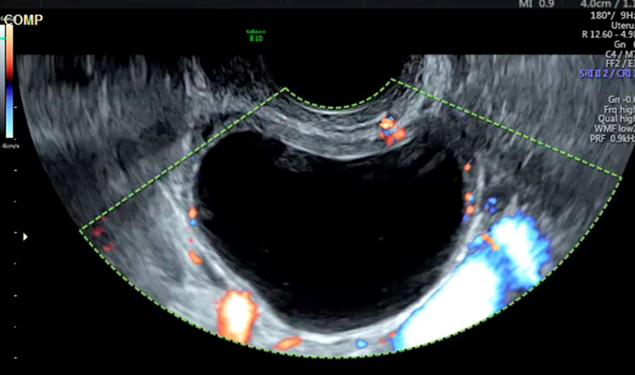

Il n’y a pas de vascularisation périphérique anarchique sur cette image. Le gros vaisseau prenant le signal Doppler correspond à l’artère iliaque interne.

L’échographie pelvienne est la suivante (fig. 4).

Figure 4 (Rodolphe Matias de Sousa, La Revue du Praticien)

La douleur brutale post-rapport sexuel, l’instabilité hémodynamique, l’aspect d’hémorragie intra-kystique avec cet aspect hétérogène « en toile d’araignée » du kyste et l’hémopéritoine doivent faire évoquer une rupture hémorragique du kyste.